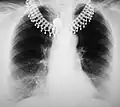

Рентгенография грудной клетки

Рентгенограмма грудной клетки в прямой проекции, норма.

Рентгеногра́фия органов грудной клетки — классическое проекционное рентгенографическое исследование грудной клетки, применяемое для диагностики патологических изменений грудной клетки, органов грудной полости и близлежащих анатомических структур. Рентгенография грудной клетки является одним из наиболее распространённых рентгенографических исследований.